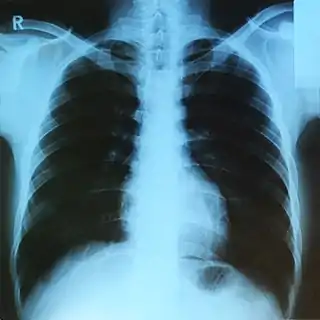

- При помощи рентгеновских лучей можно «просветить» человеческое тело, в результате чего можно получить изображение костей, а в современных приборах и внутренних органов (см. также рентгенография и рентгеноскопия). При этом используется тот факт, что у содержащегося преимущественно в костях элемента кальция (Z = 20) атомный номер гораздо больше, чем атомные номера элементов, из которых состоят мягкие ткани, а именно водорода (Z = 1), углерода (Z = 6), азота (Z = 7), кислорода (Z = 8). Кроме обычных приборов, которые дают двумерную проекцию исследуемого объекта, существуют компьютерные томографы, которые позволяют получать объёмное изображение внутренних органов.